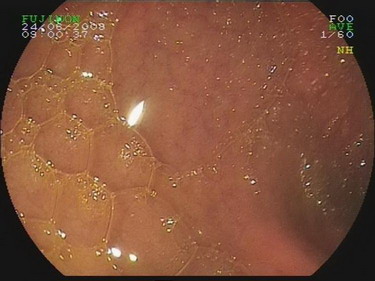

2009.6.24胃镜:

慢性浅表性胃炎,十二指肠淤滞症原因待查,肠系膜上动脉压迫综合症?(胃内可见胆汁样物反流,十二指肠球扩张,降部明显扩张,水平部远端似可见狭窄,持续充气肠腔不能打开。)